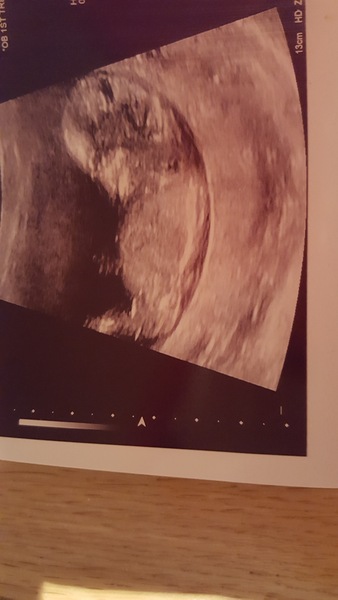

Masweetpea1 · 22/11/2016 19:40

Congrats on all the scans today!

Here's mine, 12+2. The internal bleed has gone!! Smile I have a fibroid which is giving me pain but nothing to worry about. Baby is looking good, downs test results in a week.

Really pleased, was absolutely dreading it! Just have the next 28 weeks to get through!!

Lovely pic sweet. Glad it went well

sweet great pic! Good bleeding has stopped xx